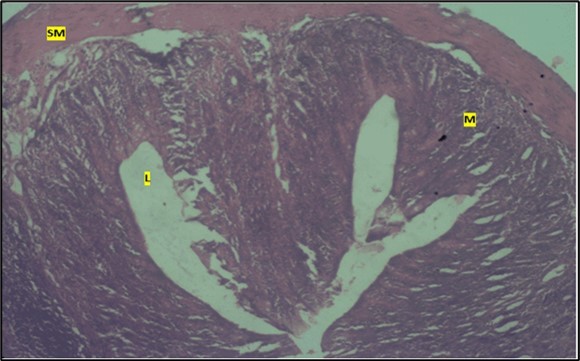

Micrographs of The Large Intestine

Results from the large intestine histological observation showed normal appearance of epithelial cells lining the mucosa with no pathological observations in control animals (Figure 5). However, administration of Abelmoschus esculentus at low dose showed dysplasia of cells and loss of normal epithelial shape (Figure 6) and the high dose group showed mild dysplasia (Figure 7)

Figure 7.High dose showing the lumen (l), the smooth muscle layer(sm). mucosa (m) shows mild dysplasia H & E. X40.